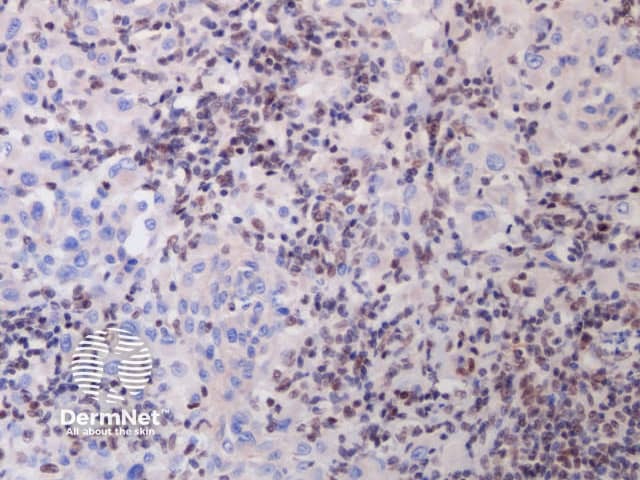

A BAP1-inactivated melanocytic tumour is BAP1 negative (biallelic loss) and has melanocytes. Note there is a loss of BAP1 expression on immunohistochemistry (IHC) of larger epithelioid melanocytes, while regular melanocytes retain BAP1 expression (figure d).

d. x 20, immunohistochemistry

BAP1-deficient lesion. Male 14, back with a pedunculated lesion. Images supplied by Professor Richard Scolyer.